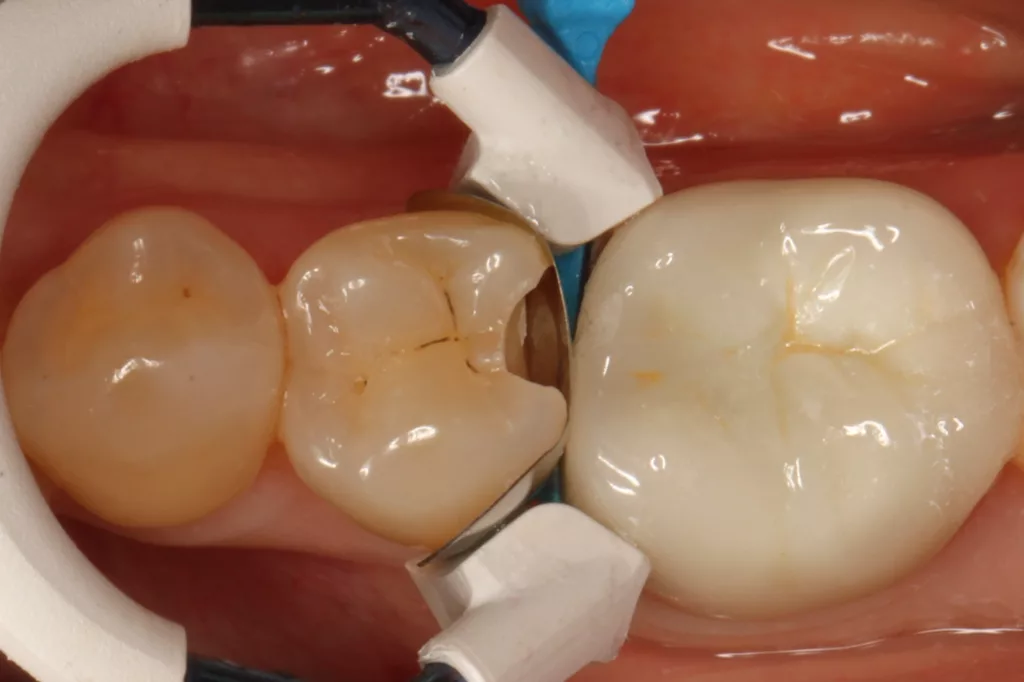

Fall 5: Versorgung einer okklusalen Kavität an einem unteren Molaren

Auch im Molarenbereich können Bulkflow-Materialien effektiv und ökonomisch eingesetzt werden, ohne Abstriche an der Ästhetik machen zu müssen, was der Fall des hier versorgten Zahnes 46 bei einer 22-jährigen Patientin zeigt. Die Abbildung 24 stellt die bereits präparierte und mit einem Einzelzahnkofferdam isolierte Kavität mit der Phosphorsäurekonditionierung der Schmelzränder (Gel Etchant, Kerr) dar. Die Entscheidung zur absoluten Trockenlegung fiel aufgrund der nicht so einfach kontrollierbaren Zunge und der vielen Schluckreflexe, was das Risiko einer ungewollten Speichelkontamination der Klebefläche unverhältnismäßig erhöhte.

Die Verwendung des Kofferdams ist generell eine sehr empfehlenswerte, aber keine zwingende Voraussetzung zur Etablierung einer suffizienten Kontaminationskontrolle [47,96]. Das bisher auch bereits verwendete Zwei-Schritt-Universaladhäsiv G2 Universal wurde hier in der selektiven Schmelzätztechnik angewendet, d.h., das Material arbeitet auf dem Dentin selbstkonditionierend (Abb. 25). Die bislang zu diesem innovativen Mehrflaschen-Universaladhäsiv publizierten Daten zeigen eine beeindruckende Performance, die den Vergleich mit sogenannten Goldstandards [98] wie einem Optibond FL nicht scheuen müssen [13,18,34,58,63,114,119,127,130]. Im nächsten Schritt wurden die einzelnen Höcker mit dem angenehm standfesten Flowable aufgebaut (Abb. 26). Die Abbildung 27 zeigt die komplett versorgte okklusale Kavität, die Abbildung 28 die Situation unmittelbar nach Ausarbeitung und Politur. Erneut beeindruckt die gute Farbadaptation.